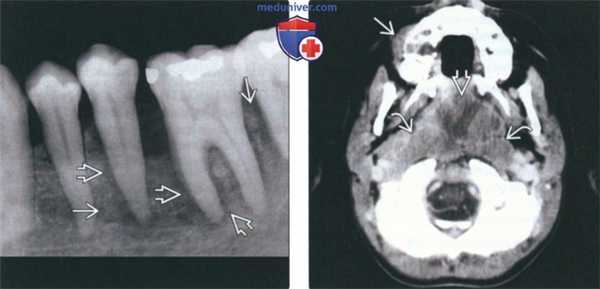

(Слева) На периапикальной рентгенограмме определяется лимфома Беркитта с поражением задних отделов нижней челюсти слева. Изменения на рентгенограмме неспецифичны для лимфомы Беркитта и отражают признаки злокачественности, такие как пермеативная деструкция кости и симметричное расширение пространств периодонтальной связки.

(Справа) На аксиальной КТ с КУ у пациента с лимфомой Беркитта определяется поражение верхней челюсти и сопутствующая ему мягкотканная опухоль. Обратите внимание на распространенное поражение аденоидов и заглоточных лимфоузлов.

2. Рентгенография при лимфоме Беркитта челюсти:

• Рентгенологические признаки:

о Плохо отграниченная экспансивная опухоль челюсти с «пестрой» картиной пермеативной деструкции кости

о Возможно баллонообразное вздутие, сопутствующее мягкотканное образование:

- При поражении надкостницы может возникать лучистая периостальная реакция

о Смещение прорезавшихся зубов и зубных зачатков в криптах, расширение фолликулярных пространств, расширение пространств периодонтальной связки

о Деструкция кортикальных пластинок фолликула и твердой пластинки зубов, истончение или разрушение кортикальных пластинок

о Зубы, «плавающие в пространстве»; прорезывание формирующихся зубов без корней или с недоразвитыми корнями

о Поражение часто множественное, может быть двухсторонним